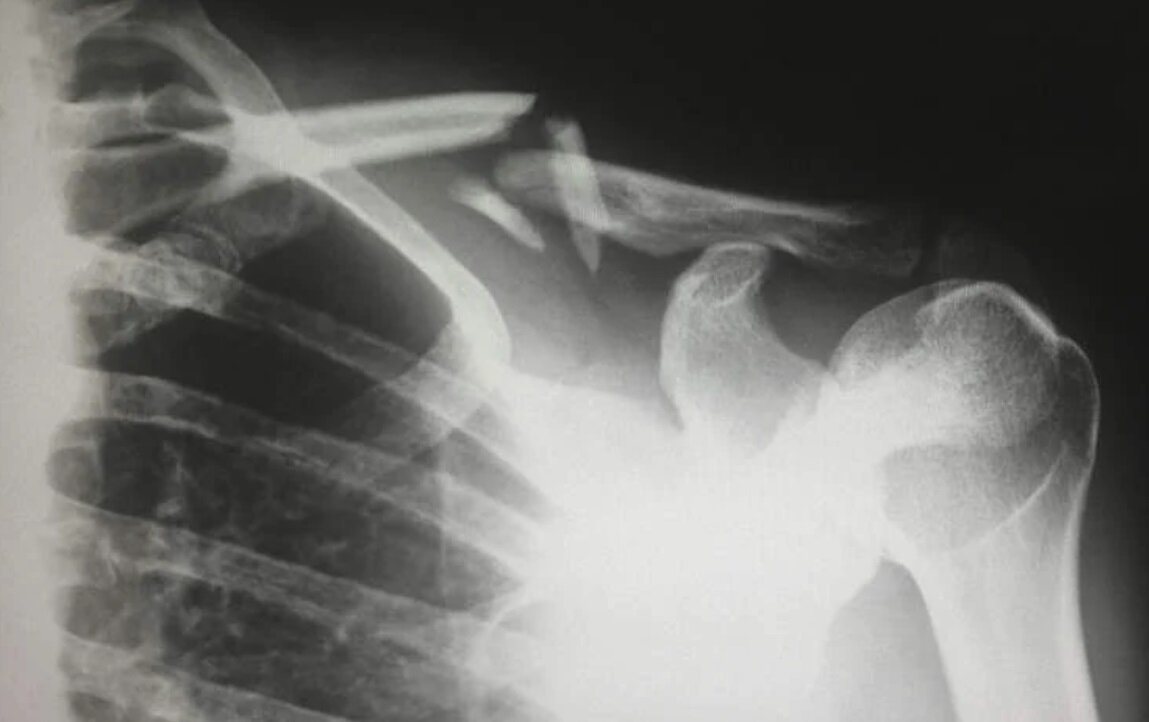

کمبود این ویتامین، این زن را به پوکی استخوان مبتلا کرد تاجاییکه هنگام غلت زدن در رختخواب موقع خواب، چند تا از استخوانهایش شکست.

کمبود ویتامین دی موجب از دست رفتن تودههای استخوانی و درنتیجه پوکی شدید استخوان در این زن شده است.